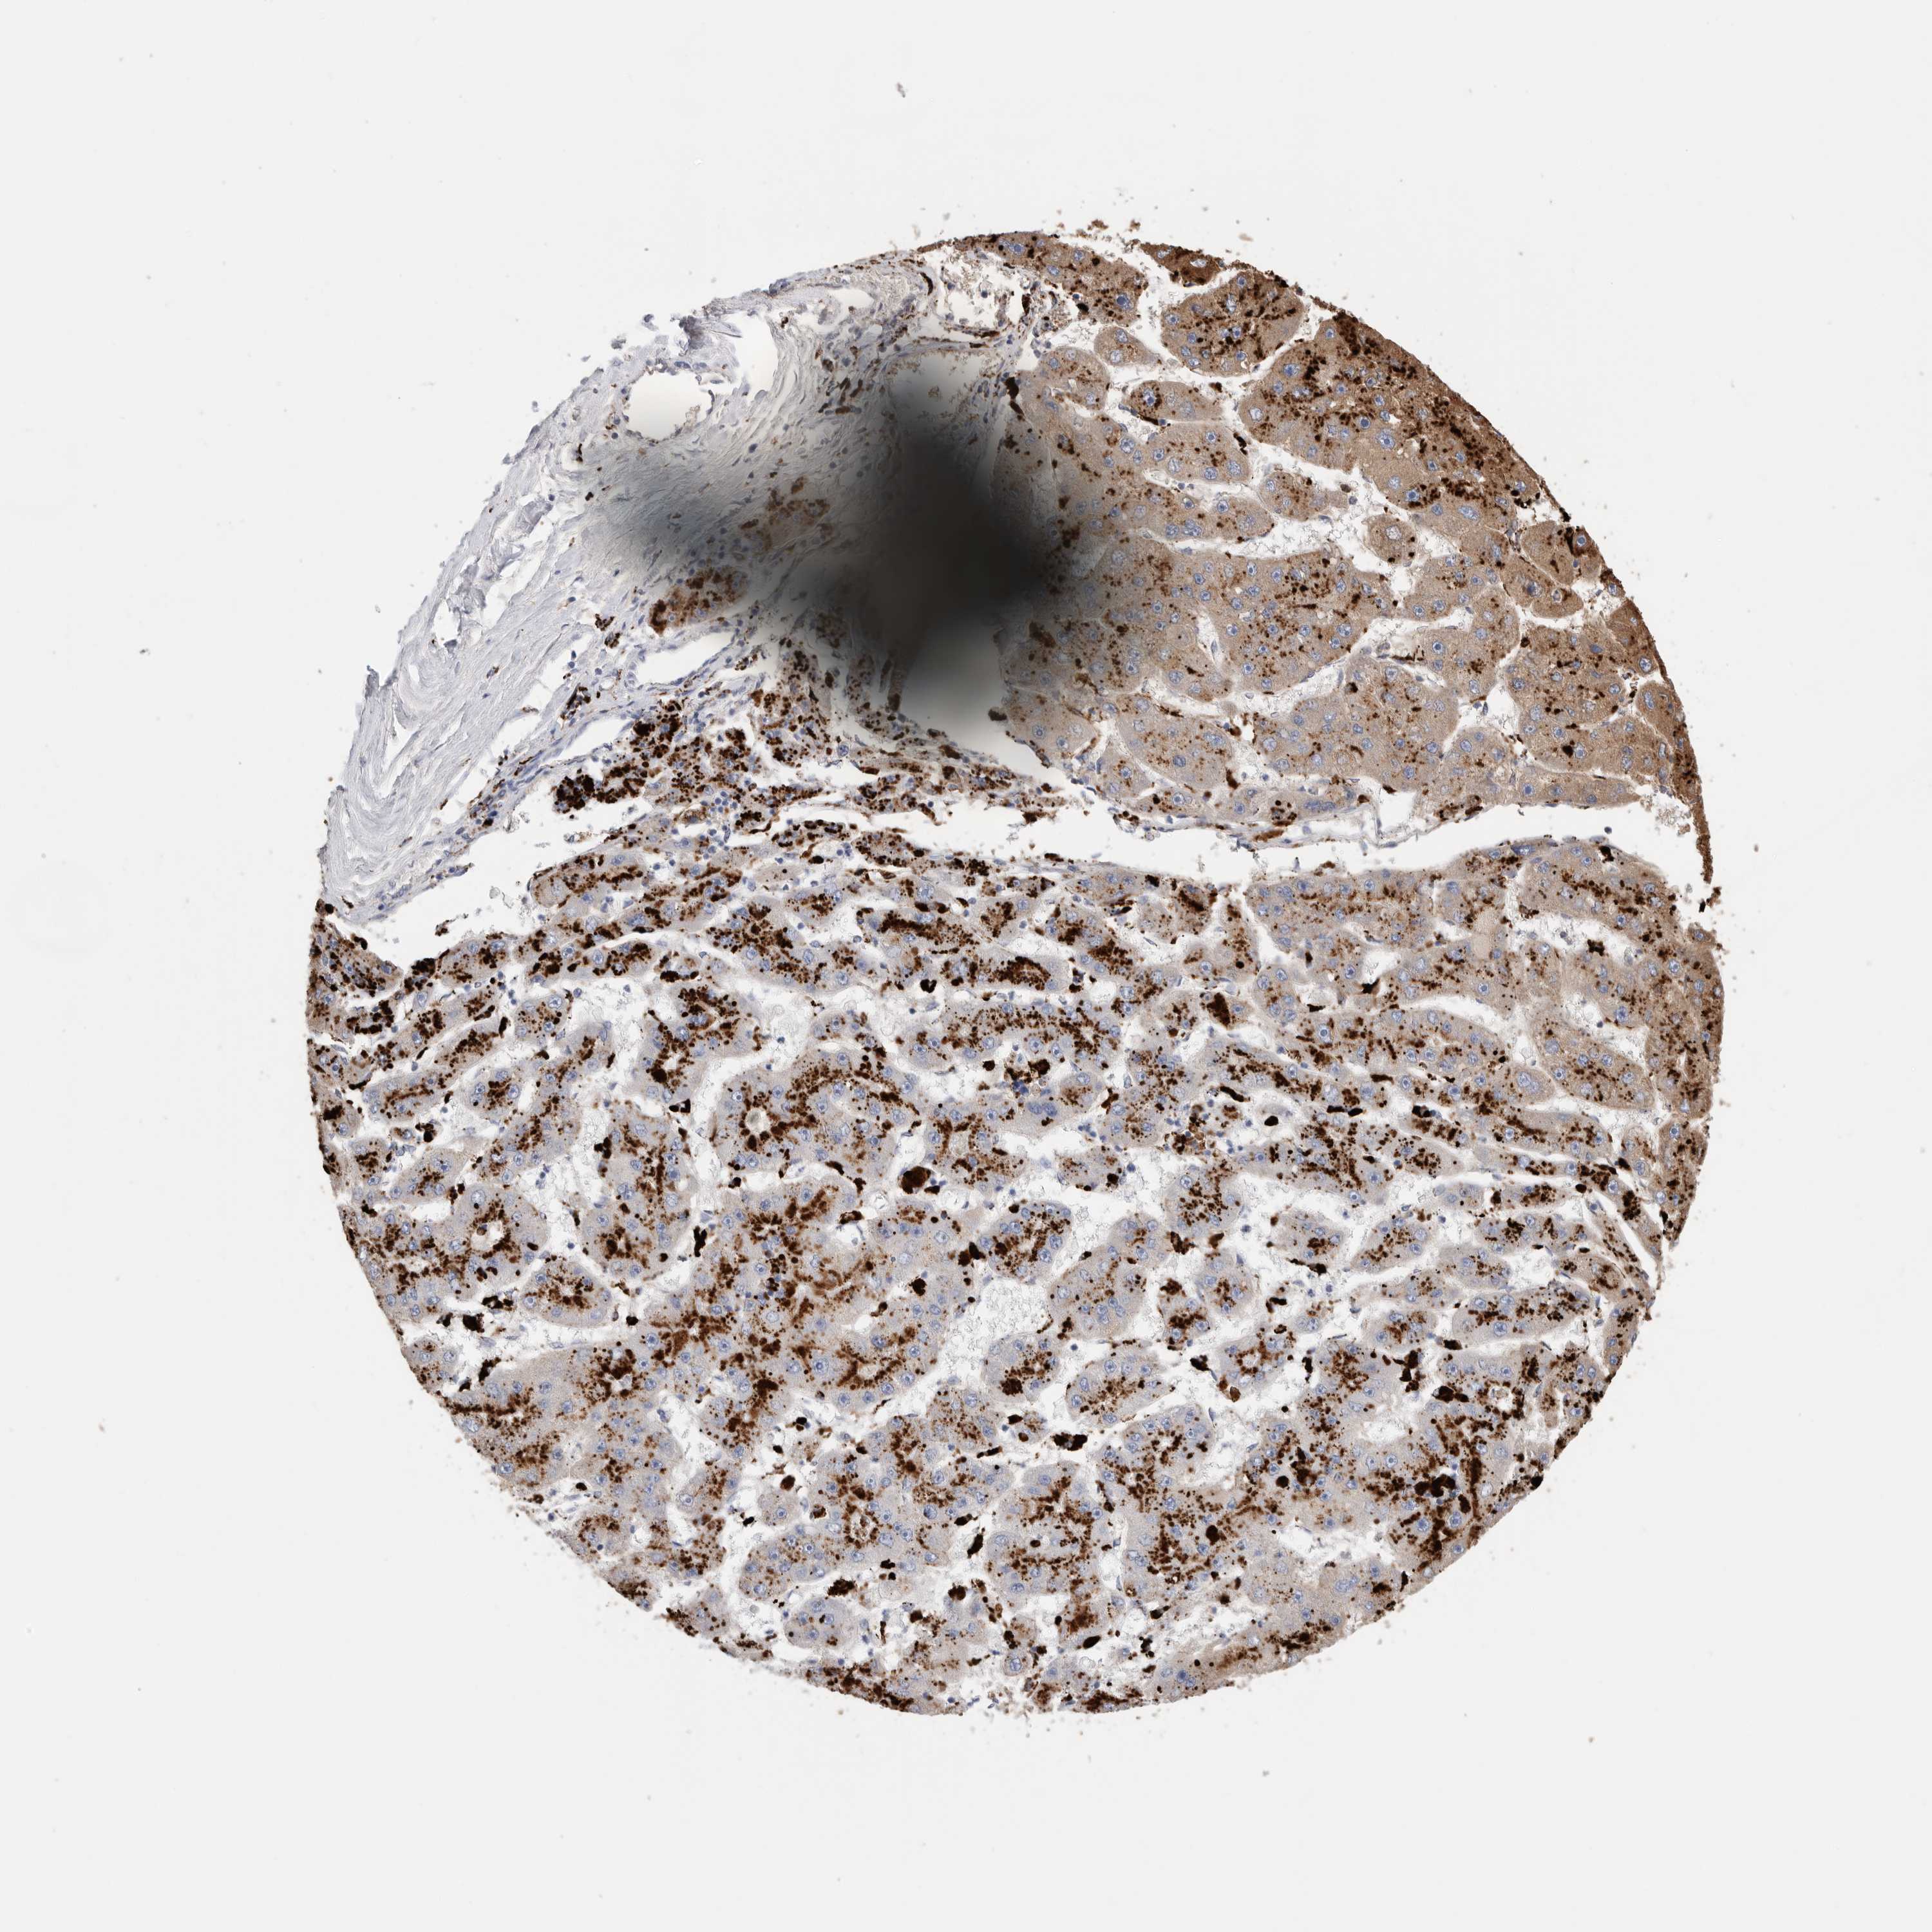

LIVER CANCER - Protein expressioni

A mouse-over function shows sample information and annotation data. Click on an image to view it in a full screen mode. Samples can be filtered based on level of antibody staining by selecting one or several of the following categories: high, medium, low and not detected. The assay and annotation is described here.

Note that samples used for immunohistochemistry by the Human Protein Atlas do not correspond to samples in the TCGA dataset.

Antibody stainingi

Antibody staining in the annotated cell types in the current human tissue is reported as not detected, low, medium, or high, based on conventional immunohistochemistry profiling in selected tissues. This score is based on the combination of the staining intensity and fraction of stained cells.

Each image is clickable and will lead to virtual microscopy that enables deeper exploration of all samples and also displays staining intensity scores, fraction scores and subcellular localization as well as patient and tissue information for each sample.

Antibody HPA025226

Antibody CAB019296

Staining

High

Medium

Low

Not detected

Intensity

Strong

Moderate

Weak

Negative

Quantity

>75%

75%-25%

<25%

None

Location

Nuclear

Cytoplasmic/membranous

Cytoplasmic/membranous,nuclear

Cholangiocarcinoma

Carcinoma, Hepatocellular, NOS